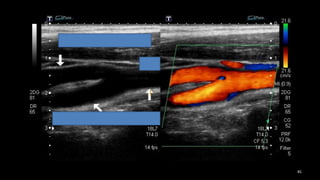

• 2. Imágenes longitudinales

con color para identificar

de enfermedad.

• Giro 90°, incluso recurrir a

planos posteriores (v.gr.

Cercano a mastoides).

• Muy útil para identificar

características de los flujos.